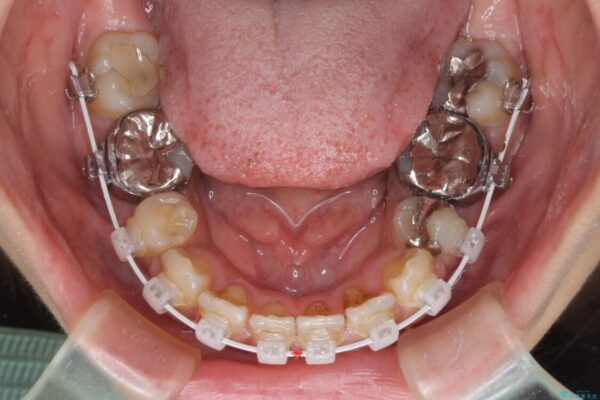

治療途中

• デコボコと口元の突出感 ハーフリンガルでの抜歯矯正 治療途中画像

目立たない装置を希望されたので、上顎が裏側装置のハーフリンガルを選択し、上下左右の小臼歯(計4歯)を抜歯して矯正治療を行うこととしました。